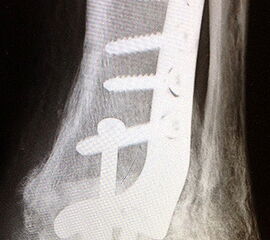

Die Verwendung von präformierten winkelstabilen Titan-Konturplatten gewährleist eine sehr rigide Versorgung und stellen gerade bei malazischem Knochen oder der Erfordernis einer frühen sehr hohen Stabilität ein sicheres allerdings kostenintensives Verfahren dar (Abb. 8 a-k, Abb. 9 a - d). Von der Industrie werden verschiedene Plattensysteme angeboten, teilweise mit polyaxialer Schraubenplatzierung, sowie die bedarfsweise Kombination einer gelenküberschreitenden Zugschraube mit winkelstabilen Schrauben.

Abbildung 8a

Abbildung 8b

Abbildung 8c

Abbildung 8d

Abbildung 8e

Abbildung 8f

Abbildung 8g

Abbildung 8h

Abbildung 8i

Abbildung 8j

Abbildung 8k